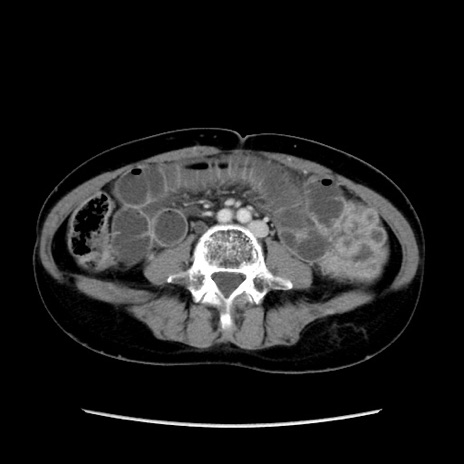

症例32(横断像)

【症例】40歳代 女性

【主訴】上腹部痛、嘔気・嘔吐

【現病歴】約9時間前頃から急に上腹部痛、嘔気、嘔吐が出現。改善しないため救急要請。

【既往歴】子宮頚癌(広汎子宮全摘術、放射線療法)、腸閉塞